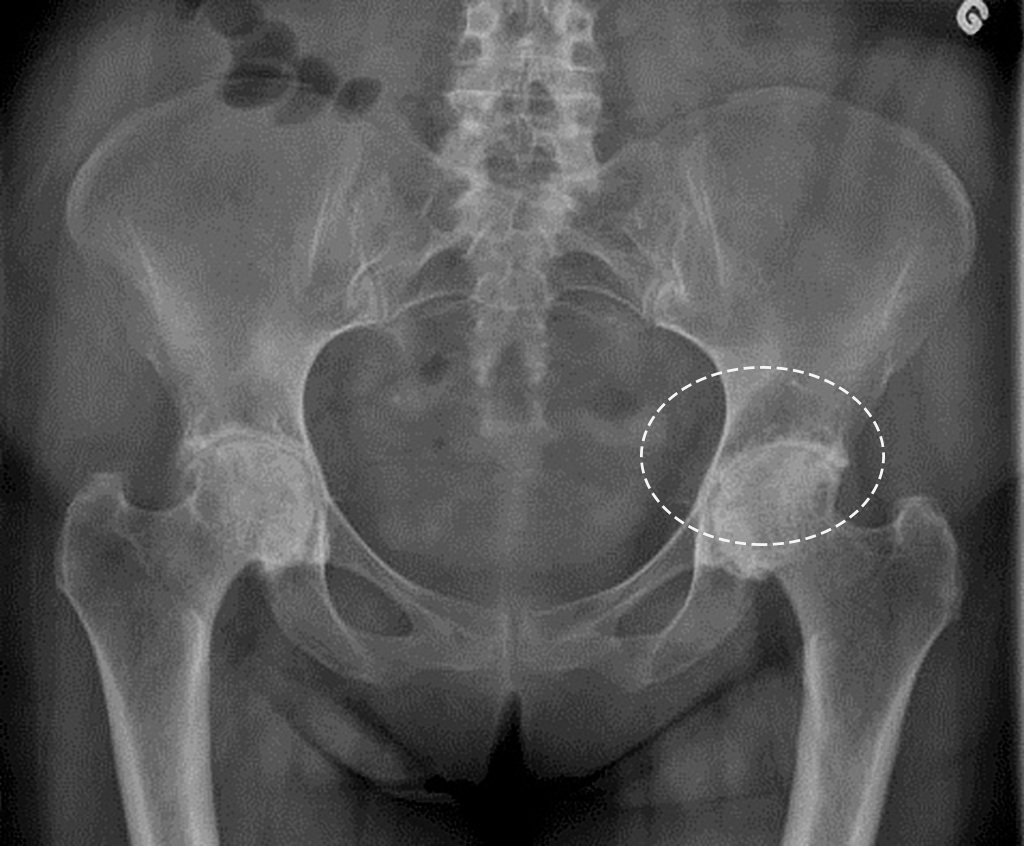

영상 검사

진단이 필요할 경우, 의사는 X-레이, MRI, CT 스캔과 같은 영상 검사를 권장할 수 있습니다. X-레이는 관절의 뼈 구조를 확인하는 데 유용하며, MRI는 연골, 인대, 신경 등의 상태를 보다 상세히 파악할 수 있습니다. 이러한 영상 검사는 통증의 원인을 파악하는 데 필수적입니다.